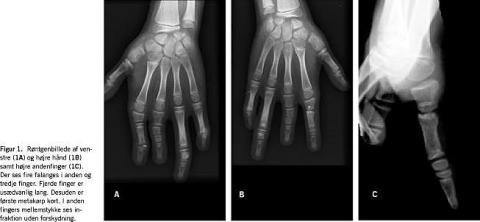

To år senere henvendte patienten sig til skadestuen pga. fraktur af højre anden fingers mellemstykke. Frakturen var forårsaget af boldspil i skolen. En røntgenundersøgelse af begge hænder suppleret med en røntgenundersøgelse af fødderne viste polyfalangisme på såvel hænder som fødder (Figur 1 ). Barnet havde fortsat ingen gener af sin anomali, hverken fra hænder eller fødder. Desværre har vi pga. patientens manglende kontakt til sin biologiske far ikke mulighed for at kortlægge sygdommen hos eventuelle biologiske halvsøskende på faderens side.

Syndromet har fem anatomiske særkender: 1) polyfalangisme sædvanligvis med fire falanges i den midterste finger og næsten altid også i pegefingeren. Den ekstra falanks danner en ekstra bøjefure volart, og den klinisk diagnose kan stilles på denne måde. Det ekstra led kan medføre hypermobilitet af fingeren [4]. Findes et øget antal falanges i tommelfingeren kaldes det trefalangeal tommel [1]; 2) brakyfalangisme eller forkortelse af de afficerede fingre og tæer; 3) den proksimale falanks af ringfingeren er abnorm lang; 4) leddannelse mellem basis af den proksimale falanks af pegefingeren og mellemhåndsknoglen kan medføre ulnar deviation af pegefingeren og 5) kort pegefinger.

Anomalien findes i mange forskellige variationer, og vor patient afveg fra den hyppigste variation af denne i øvrigt sjældent forekommende misdannelse ved ikke at have en ekstra falanks i tommelfingeren, men derimod en kort første metakarpalknogle.